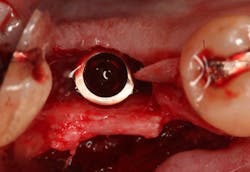

Excellent interseptal bone width was present, both buccal and lingual plates were present, and an adequate amount of bone was present coronal to the inferior alveolar nerve to allow for immediate implant placement. A sulcular incision was made around K and the adjacent teeth, and a full-thickness buccal and lingual flap was reflected. The tooth was sectioned in half, and the mesial and distal roots were elevated. The socket was degranulated with a round diamond bur and copiously irrigated with chlorhexidine gluconate 0.12% rinse. An osteotomy was completed in the interseptal area, and a bone-level 4.8- x 10-mm implant was placed to 35 Ncm. A mixture of cancellous and cortical allograft was infused with autogenous plasma-rich growth factor (PRGF), which was isolated during a preprocedural blood draw. The mixture was packed into the residual socket, slightly coronal to the implant platform to account for predictable resorption during healing. (13)

A 15- x 20-mm Ossix Plus membrane was hydrated in sterile saline for three minutes and trimmed to extend roughly 3 mm beyond the buccal and lingual extent of the bone graft and roughly 1 mm from the adjacent teeth. A sterile template is included in each membrane package; it can be trimmed to the appropriate dimensions and superimposed on the Ossix Plus membrane for final trimming to ensure the exact dimensions desired are obtained. This membrane can also be sutured, if necessary. When this technique is used, it is important to pass the suture needle through the membrane at a 90-degree angle to avoid tearing the membrane.